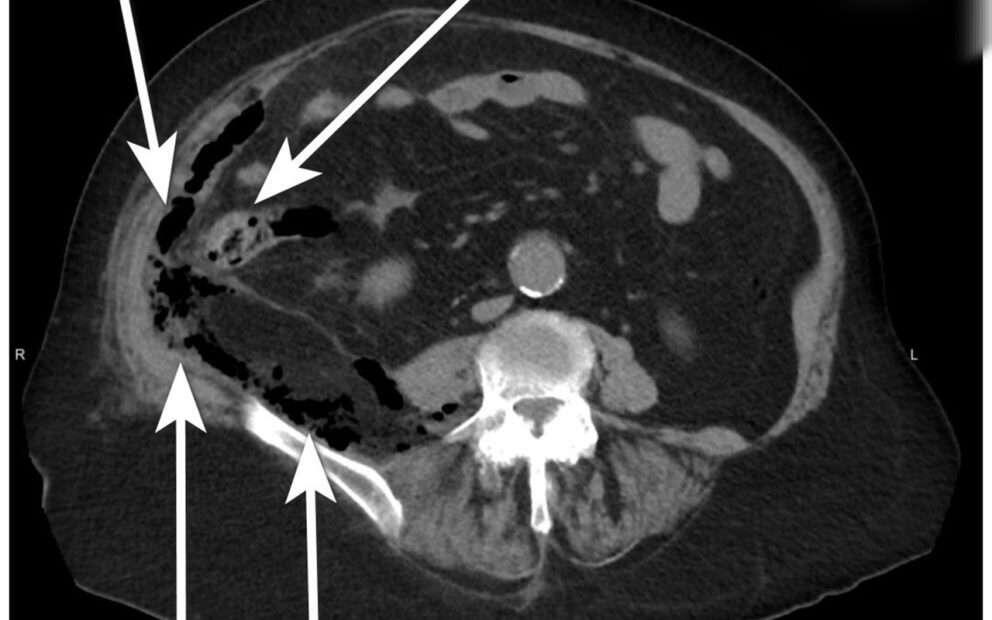

Женщина обратилась в больницу с жалобами на сильные боли внизу живота и поясницы, сопровождающиеся повышенной температурой тела. Осмотр показал наличие серьезного заболевания – острого деструктивного аппендицита, осложненного обширным воспалительным процессом в брюшной полости.

Несмотря на сложность ситуации и сопутствующие хронические болезни, хирурги оперативно вмешались, успешно устранив аппендикс и очистив все очаги гнойного воспаления. Особенность случая заключалась в сложности ведения пациента из-за многочисленных сопутствующих болезней, таких как почечная недостаточность, сердечные патологии и сахарный диабет.